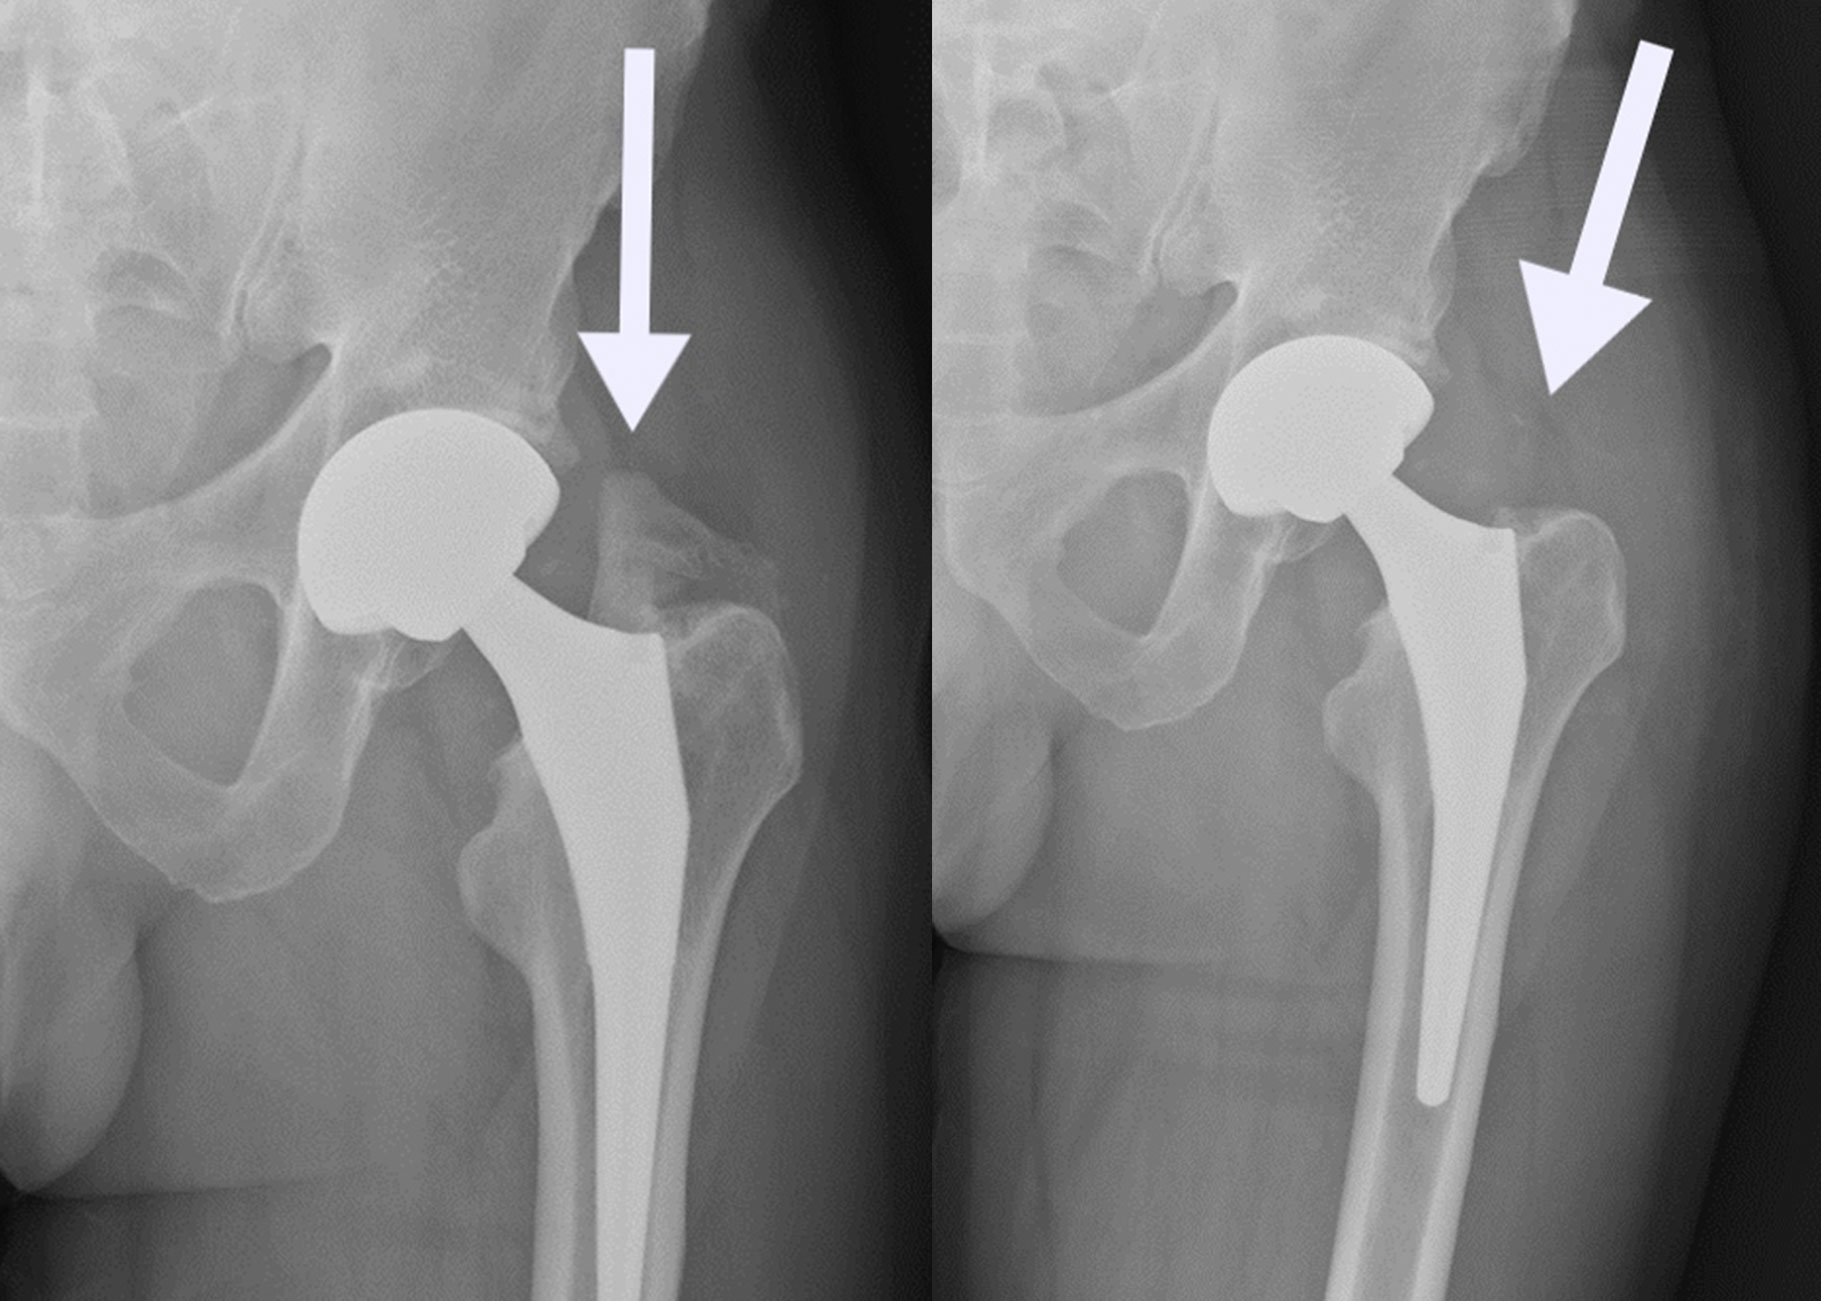

Femoroacetabular Impingement (FAI): A Major Indication for Hip Arthroscopy

Femoroacetabular impingement (FAI) is one of the most common conditions requiring hip arthroscopy surgery in Surat. FAI occurs when abnormal bone growth on the femoral head (cam impingement) or acetabulum (pincer impingement) causes repetitive collision during hip movement, leading to labral tears, cartilage damage, and progressive hip arthritis if left untreated.

Dr. Krunal Donda specializes in arthroscopic FAI correction, reshaping the bone to eliminate impingement while repairing associated labral and cartilage damage. This comprehensive hip arthroscopy approach addresses the underlying structural problem and secondary damage, preventing progression to hip arthritis and preserving the natural hip joint.

Cam impingement: Extra bone on femoral head-neck junction causing damage to cartilage during flexion movements.

Pincer impingement: Excessive acetabular coverage or retroversion causing labral crushing and rim damage.

Mixed FAI: Combined cam and pincer components — most common presentation requiring comprehensive arthroscopic correction.

Arthroscopic osteoplasty: Precision bone reshaping performed arthroscopically to restore normal hip biomechanics and joint clearance.